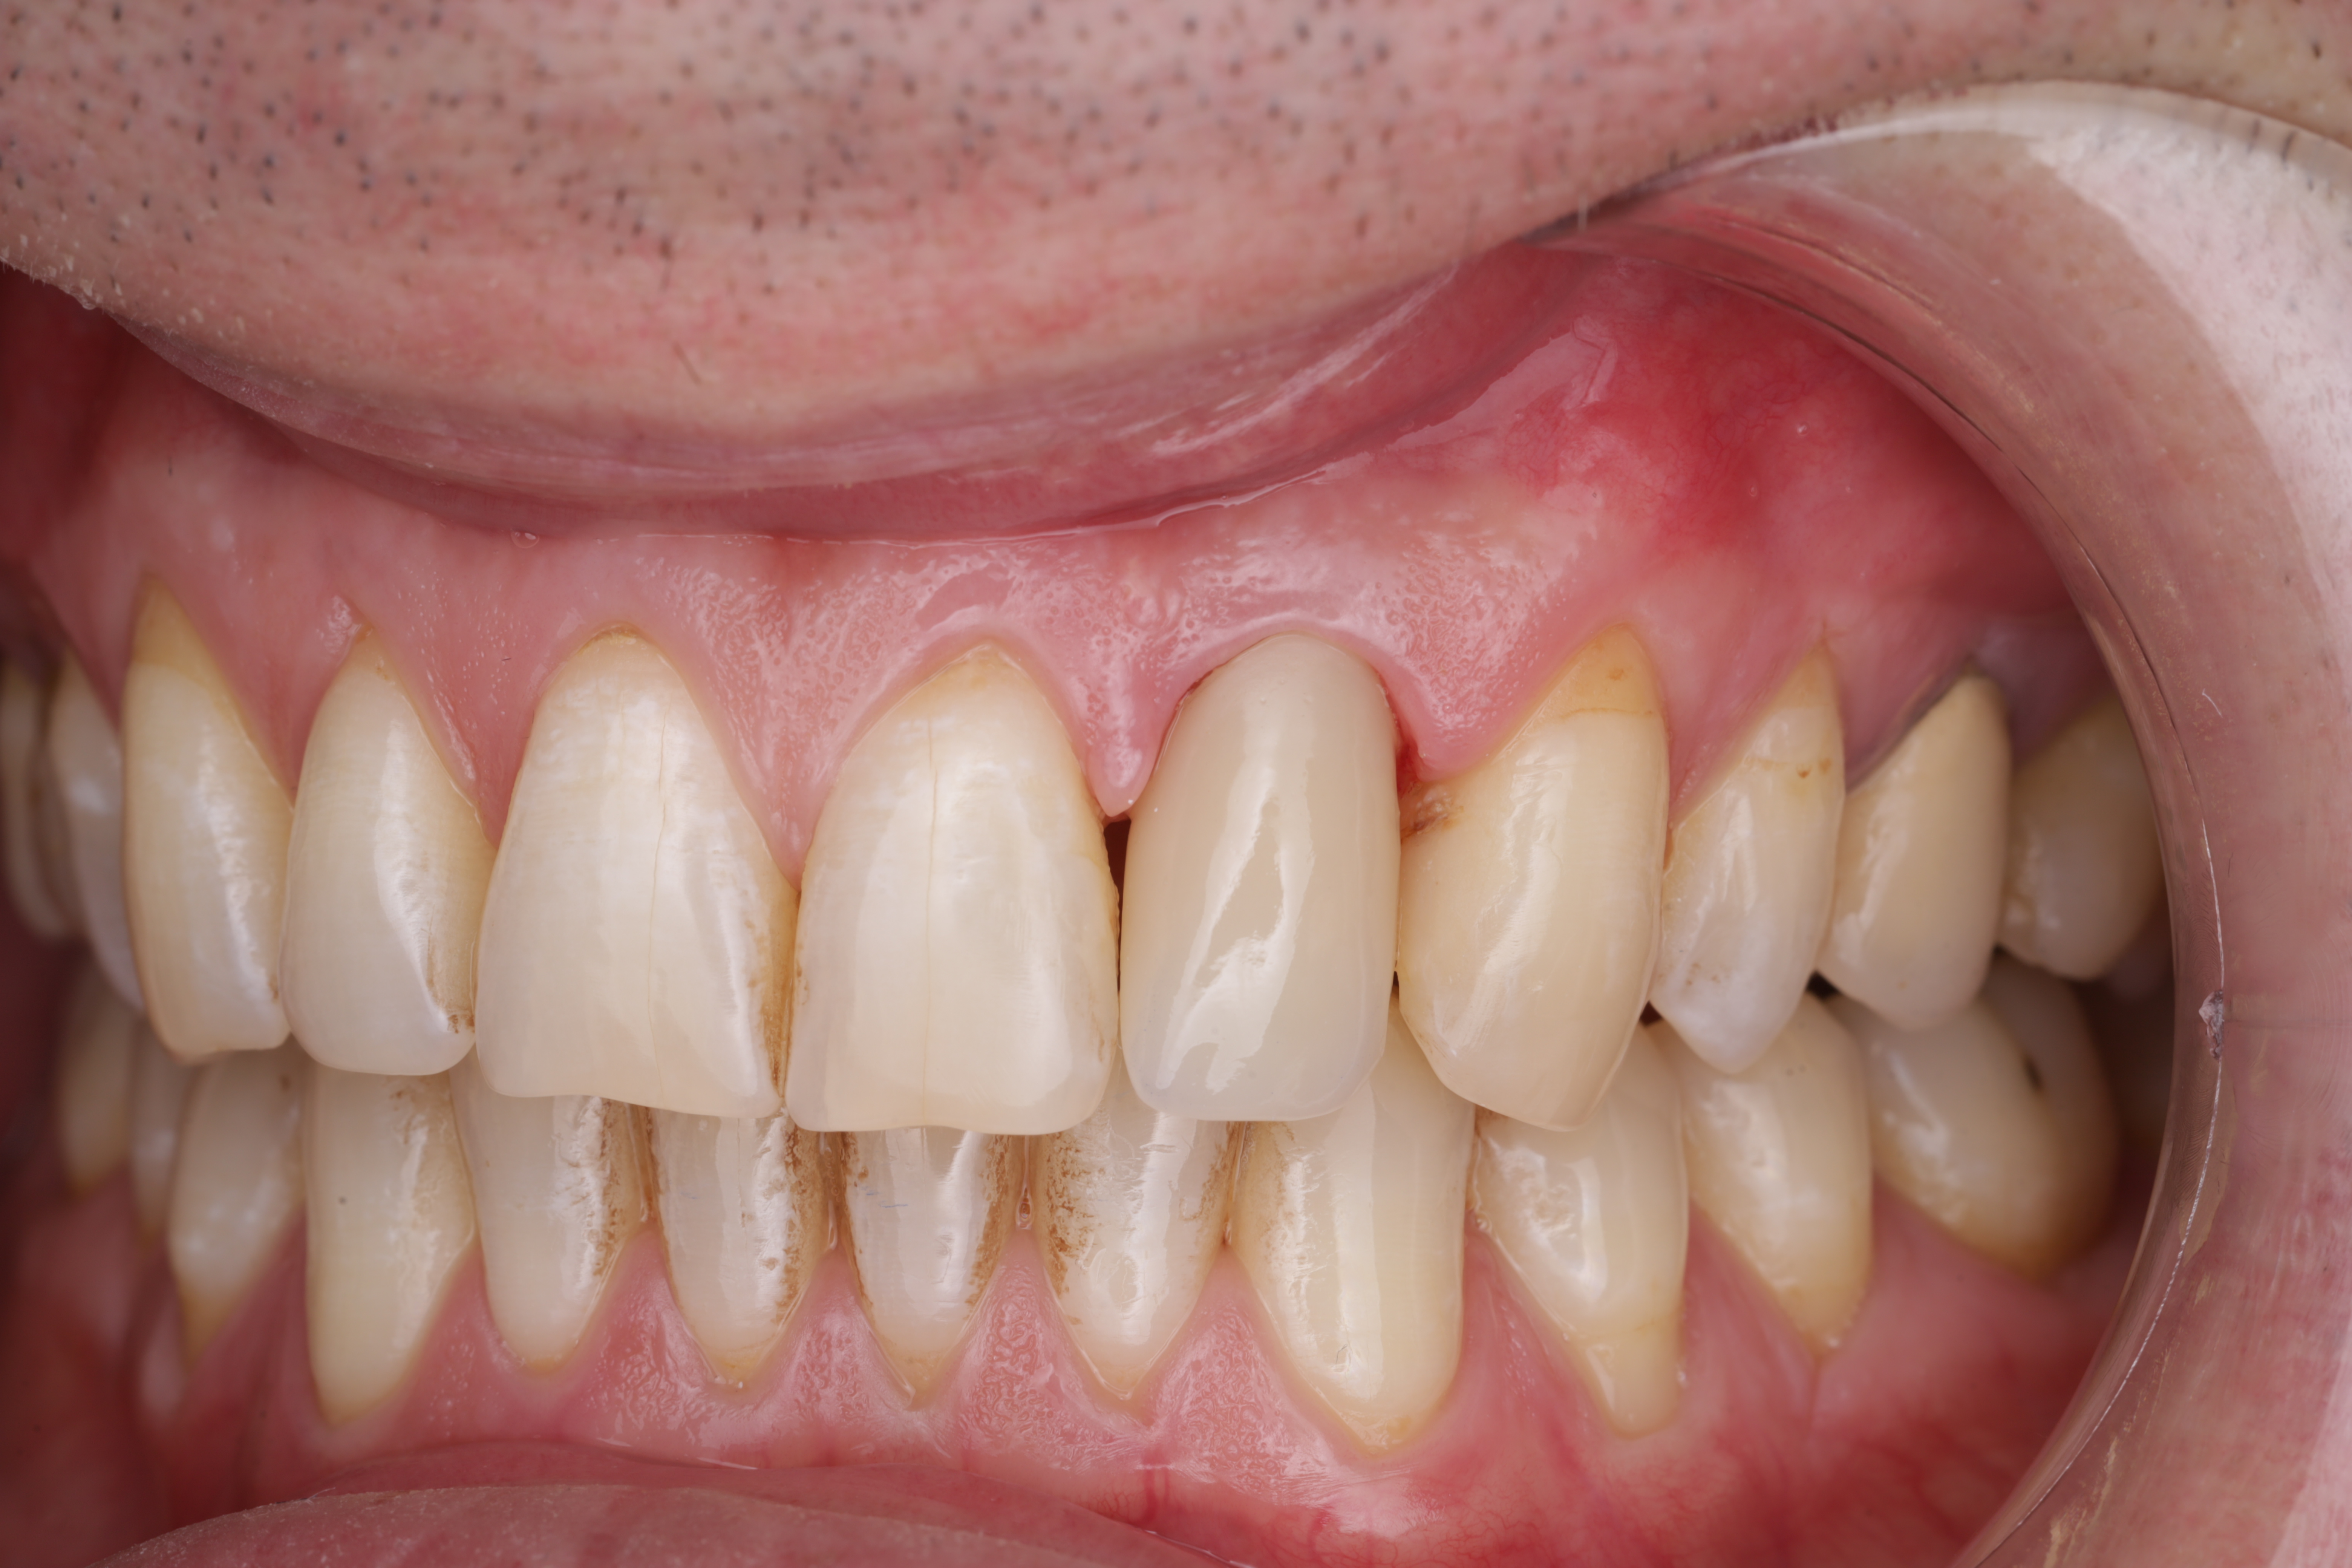

Отломок корня

Так выглядит лопнувший корень, скол уходит под уровень кости